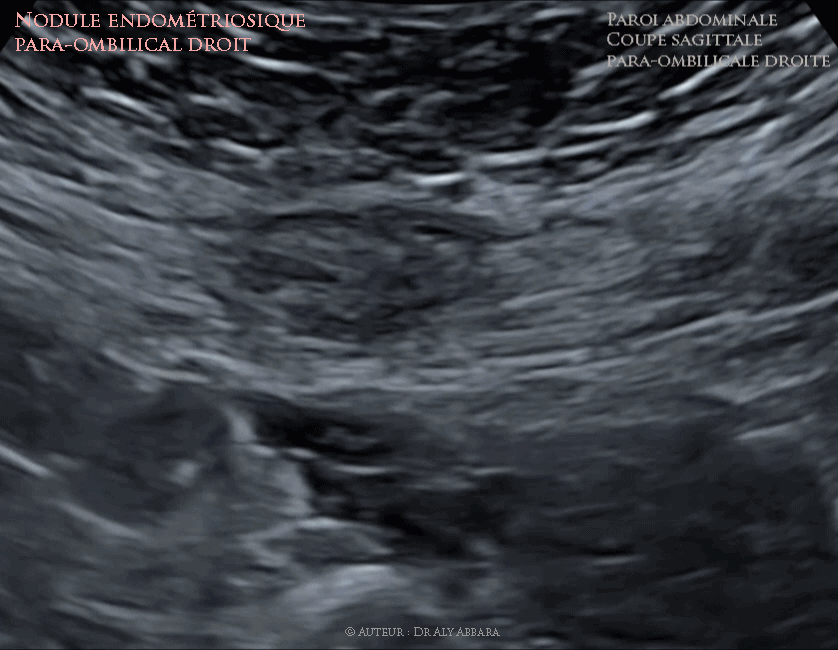

• Images échographiques animées et séquences vidéo montrant la présence d'un foyer endométriosique intra-musculaire évoluant dans le muscle grand droit abdominal droit, dans la région para-ombilicale droite et distant horizontalement de 3 cm de l'ombilic.

• Il s'agit d'un nodule hétéroéchogène (échogénicité inférieure à celle du muscle), à contours irréguliers, sans capsule périphérique et mesurant 14 x 26 x 33 mm (soit 6,4 cm3).

Par rapport aux structures tissulaires avoisinantes, il est sous aponévrotique, sus-péritonéal et intra-musculaire et difficilement perceptible à la palpation de la paroi abdominale.